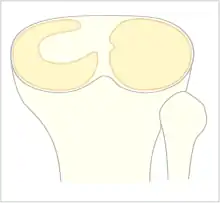

The Watanabe classification of discoid lateral meniscus is: (A) Incomplete, (B) Complete, and C) Wrisberg-ligament variant [1] Normally, the meniscus is a thin crescent-shaped piece of cartilage that lies between the weight bearing joint surfaces of the femur and the tibia. It is attached to the lining of the knee joint along its periphery and serves to absorb about a third of the impact load that the joint cartilage surface sees and also provides some degree of stabilization for the knee. There are two menisci in the knee joint, with one on the outside (away from midline) being the lateral meniscus and the inner one (towards midline) the medial meniscus. A discoid meniscus is a congenital anomaly of the knee found in 3% of the population (up to 15% in Asia). It typically affects the lateral meniscus and may be found bilaterally (20%). Instead of the narrow crescent shape, as seen in a normal meniscus above, a discoid meniscus is thickened, and has a fuller crescent shape. In addition, a discoid meniscus does not taper as much towards the center of the joint and is shaped like a disc. The thickness of the meniscus, its diminished vascular blood supply, and in some instances, weak capsular attachment, makes it more prone to tears compared to a normal meniscus. The anomaly in itself is asymptomatic; however, a tear of the meniscus can result in pain, swelling, and snapping in the affected knee. The orthopedic classification of discoid menisci includes: complete, incomplete or Wrisberg-ligament types as depicted here. Coverage of the lateral tibial plateau determines the designation of complete or incomplete. The Wrisberg-ligament type has an abnormal posterior attachment by attaching to part of the posterior cruciate ligament.